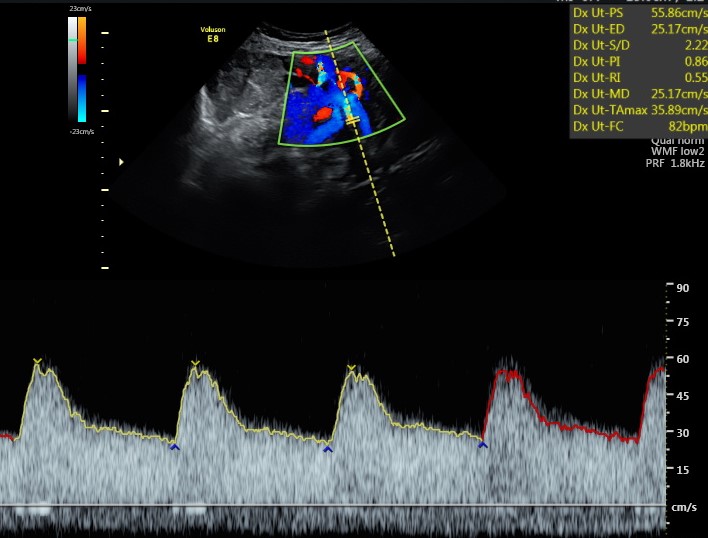

Non solo il tesoro è oggetto di valutazione, ma in questa ecografia lo è anche la mamma. Infatti, per vedere se siamo dei buoni incubatori, è importante la valutazione della resistenza delle arterie uterine.

La placenta, organo semplice strutturalmente ma dotato di una incredibile intelligenza biologica, modifica queste arterie rendendole dei vasi a bassa resistenza, assicurandosi, di conseguenza, un buon apporto di sangue per le fasi successive della gravidanza e in ultima analisi un corretto sviluppo fetale.